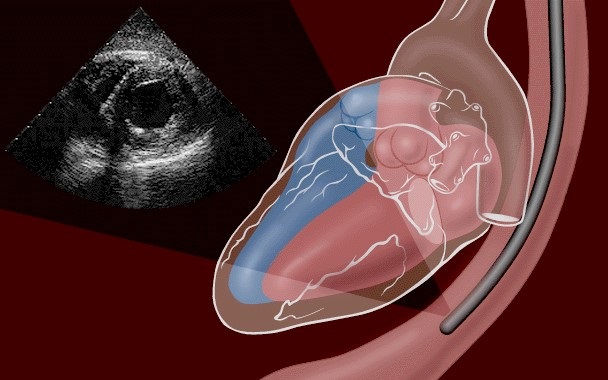

С технической точки зрения процедура аналогична гастроскопии. Пациенту через ротовую полость вводится гибкая трубка, до пищевода — органа, находящегося в непосредственной близости от сердца, без наложения других органов. В конце трубки установлен специальный ультразвуковой зонд, который поворачивается и перемещается для получения изображений с разных углов сердечных структур.

Это дает важную информацию о структурах сердца, недоступную с помощью других методов визуализации, такими как трансторакальная эхокардиография или сердечная МРТ. Трансэзофагеальная эхокардиография позволяет оценить объем крови, накачиваемой сердцем, толщину стенок, состояние перикарда (внешняя оболочка сердца), состояние клапанов и т. д.